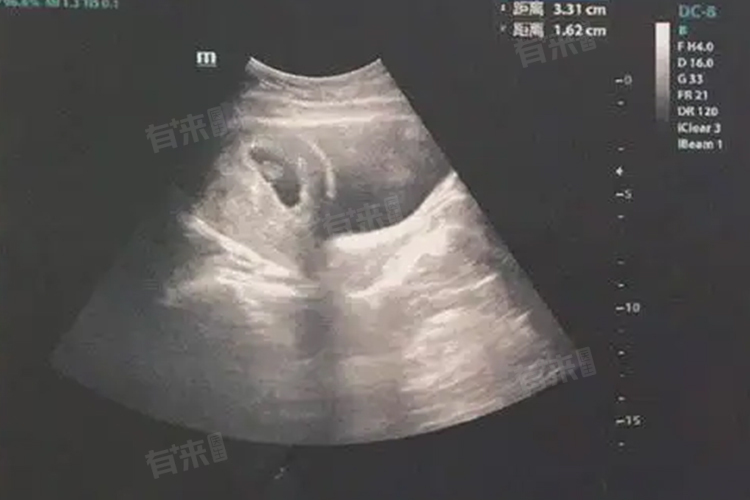

1、确认宫内妊娠:怀孕四十天,即大约孕5-6周时,通过B超检查可以清晰地观察到孕囊的位置,从而确认是否为宫内妊娠。这对于排除宫外孕风险至关重要,因为宫外孕若不及时发现和处理,可能对孕妇生命构成威胁。

2、评估胚胎发育:此时的B超检查还能初步评估胚胎的发育情况,包括胚胎的大小、形态以及是否出现胎心搏动等。这些信息有助于医生判断胚胎是否健康,以及是否需要进一步的监测或干预措施。